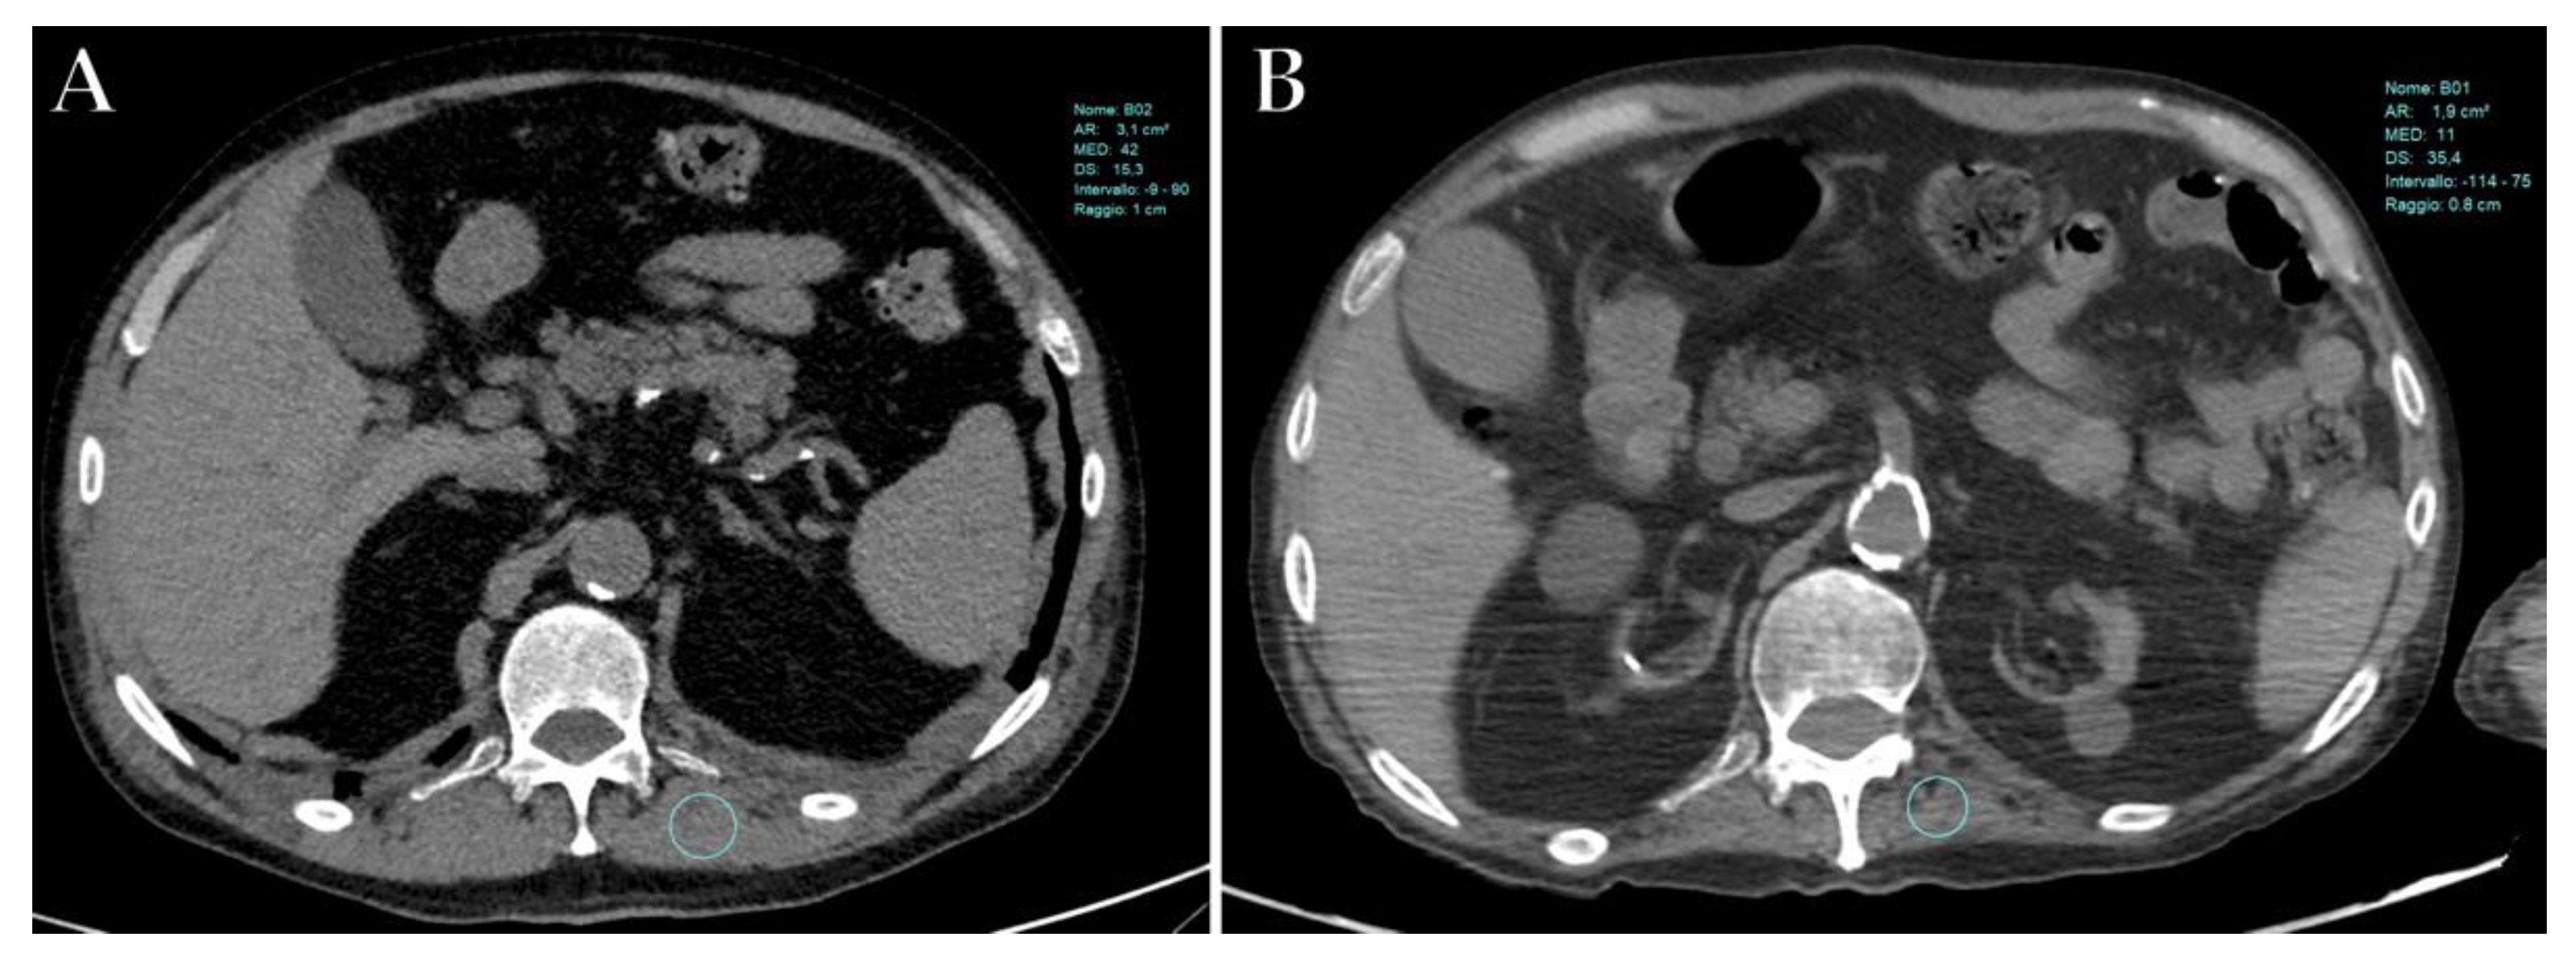

10. Sarcopenia

- Schiaffino, S.; Albano, D.; Cozzi, A.; Messina, C.; Arioli, R.; Bnà, C.; Bruno, A.; Carbonaro, L.A.; Carriero, A.; Carriero, S.; et al. CT-derived Chest Muscle Metrics for Outcome Prediction in Patients with COVID-19. Radiology 2021, 300, E328–E336. [Google Scholar] [CrossRef] [PubMed]

- Lee, K.; Shin, Y.; Huh, J.; Sung, Y.S.; Lee, I.-S.; Yoon, K.-H.; Kim, K.W. Recent Issues on Body Composition Imaging for Sarcopenia Evaluation. Korean J. Radiol. 2019, 20, 205–217. [Google Scholar] [CrossRef] [PubMed]

- Giraudo, C.; Librizzi, G.; Fichera, G.; Motta, R.; Balestro, E.; Calabrese, F.; Carretta, G.; Cattelan, A.M.; Navalesi, P.; Pelloso, M.; et al. Reduced muscle mass as predictor of intensive care unit hospitalization in COVID-19 patients. PLoS ONE 2021, 16, e0253433. [Google Scholar] [CrossRef] [PubMed]

- Damanti, S.; Cristel, G.; Ramirez, G.A.; Bozzolo, E.P.; Da Prat, V.; Gobbi, A.; Centurioni, C.; Di Gaeta, E.; Del Prete, A.; Calabrò, M.G.; et al. Influence of reduced muscle mass and quality on ventilator weaning and complications during intensive care unit stay in COVID-19 patients. Clin. Nutr. 2021, in press. [CrossRef]